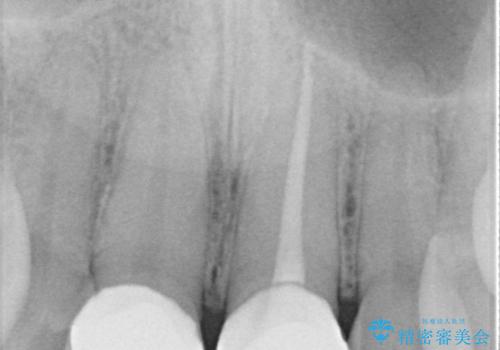

精密根管治療後、オールセラミッククラウンで治療を行いました。

治療後、違和感は無くなりました。

治療後、違和感が無くなり、被せ物で歯の長さが揃い見た目も改善されとてもご満足していただけました。